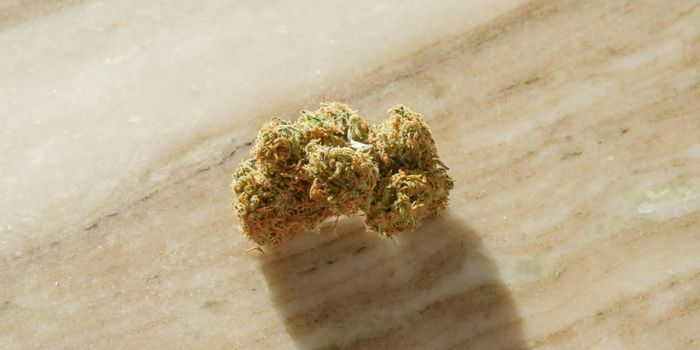

SEP 12, 2024Health & MedicineA study published in Addictive Behaviors reported that cannabis and tobacco use is increasing among older adults. The fi ...

SEP 10, 2024Health & MedicineA study published in ACS Pharmacology & Translational Science indicated that long-term THC treatment can initially e ...

SEP 05, 2024Cannabis SciencesUse of cannabis and hallucinogens remained at historically high levels in 2023 among adults aged 19- 30 years and 35-50.

SEP 05, 2024Cannabis SciencesWhat influence does cannabis legalization, whether medical or recreational, have on mental health prescription medicatio ...

SEP 04, 2024Cannabis SciencesCannabis use is relatively common among patients thinking about getting plastic surgery and is linked to higher urine ni ...